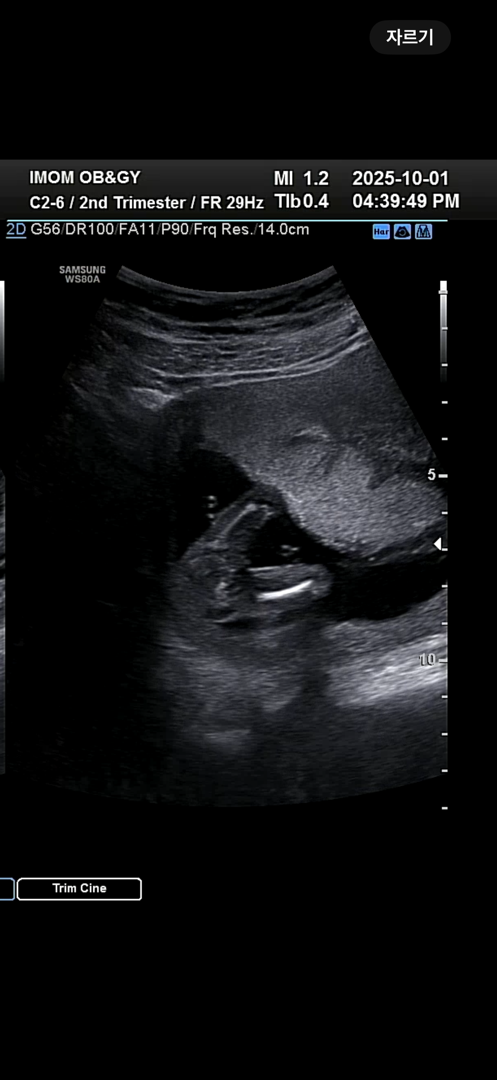

15주2일 성별확인

꺄아아아아 딸이래요!! 딸!!! 장꾸맘도 딸에 한표 주셨는데 넘넘 좋아요♥️ 20주에 제발 성별반전 없기를🥹